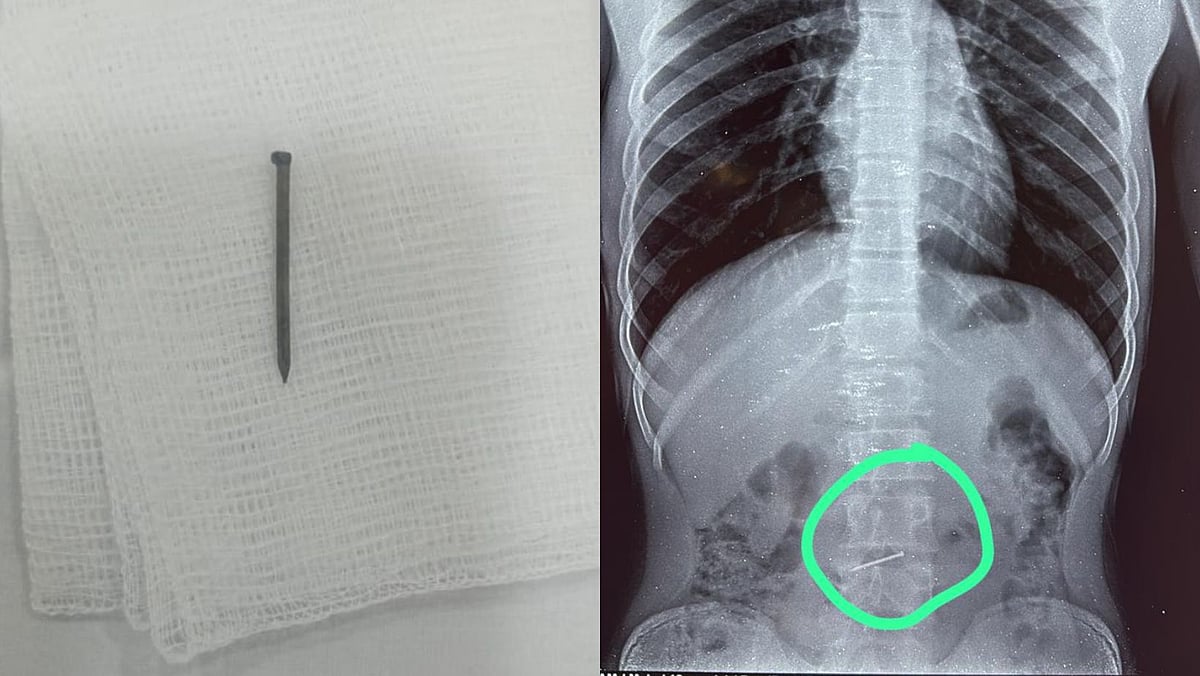

Pune: 18-Year-Old Accidentally Swallows Nail, Baner Hospital Doctors Remove It Without Surgery | Sourced

The X-ray revealed a nail in the upper part of his intestine. The sharp object posed a serious risk of internal injury. Considering the criticality of the condition, the team of doctors led by Dr Prasad Bhate, HOD and Senior Consultant – Gastroenterology, Manipal Hospital, swiftly planned to perform an emergency endoscopy procedure to remove the nail.

The patient was brought to the hospital two hours after swallowing the nail. It was easy to find the foreign object via endoscopy because the patient had not eaten anything. The nail was found at the junction of the small intestine, making its removal critical to prevent injury to the internal organs. The nail was gently removed from the body without any surgical procedure.